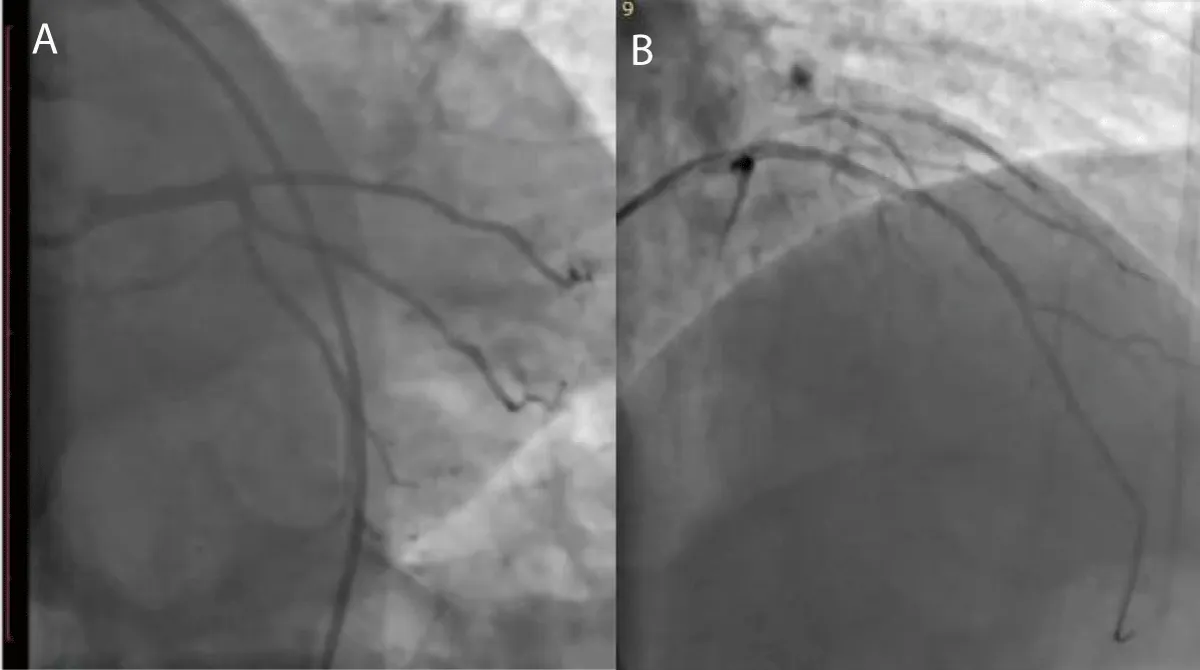

A 63-year-old male patient, previously healthy, hypertensive, diabetic and heavy smoker presented with acute burning chest pain radiating to both shoulders, which was associated with sweating and vomiting for 1 hour, but during hospitalization in the emergency room, he developed sudden onset of altered level of consciousness, dysarthria, nystagmus with National Institute of Health Scale Score (NIHS) score 12, after discussing the case we planned to do coronary and cerebral angiography. On examination the patient looks in pain, sweaty and tachypneic, and their blood pressure: was 75/40 mmHg, Electrocardiography was done and it revealed ST segment elevation in the anterior leads with ST-segment depression in I, II, AVF after that he received 300 mg of aspirin, 300 mg clopidogrel and norepinephrine 3 mcg/kg/min intravenous was started and urgently he was transferred to cardiac catheterization department for primary Percutaneous Coronary Intervention (PCI). During coronary angiography, it showed total occlusion of the proximal left anterior descending artery, stenting was done successfully by using resolute integrity 2.75 x 22 mm drug-eluting stent (Figure 2), then cerebral angiography showed normal anterior and middle cerebral circulation, but there was severe right vertebral artery stenosis, so angioplasty to vertebral artery was planned and it was done successfully (Figure 3), echocardiography was done and it showed reduced left ventricular Ejection Fraction about 30% - 35%, but no left ventricular thrombus was detected, then the patient was followed for 3 days at the hospital and he was discharged on Dual antiplatelet and he had mRS (0) with regular follow up at the outpatient clinic for 3 months, he had the good general condition and functioning well without any neurological deficit mRS (0).

Figure 2: A-coronary angiography shows proximal LAD total occlusion, B-after stent implantation in ostial LAD.